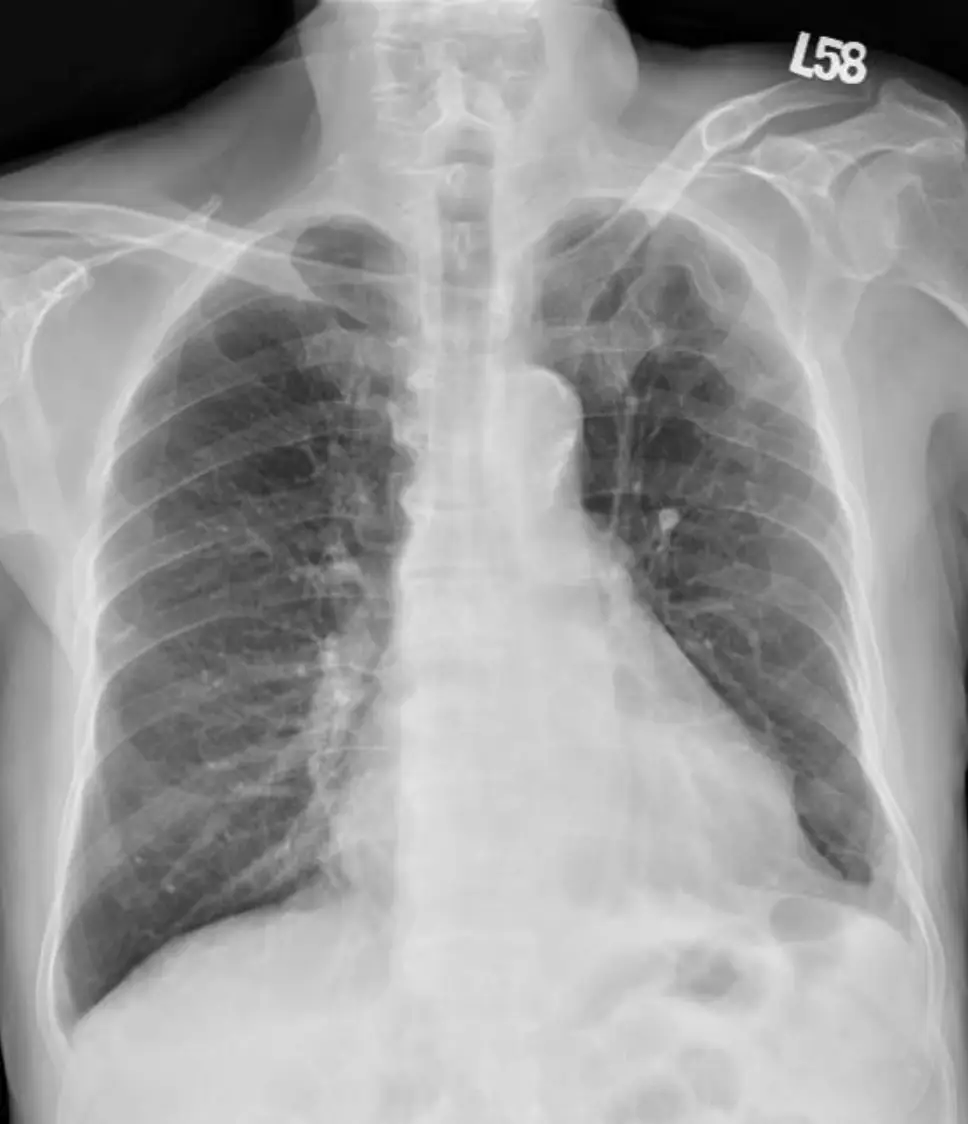

病人王先生現年88歲,有兩個月的雙腳浮腫及運動性呼吸困難,數度前往多家醫院求診,診療罔效。病人 有多年高血壓、高脂血、慢性腎臟病及前列腺肥大等過往病史。到診時意識清醒, T/P/R: 35.5 °C/99/18; BP: 106/83 mmHg; SpO₂: 92%。(ambient air); BH: 165 cm; BW: 66 kg; BMI: 24.2 kg/m² 理學檢查發現 顏面微腫,頸靜脈中度怒張,脈搏稍弱,並未有顯著Paradoxical pulse, 及Kussmaul sign,呼吸聲清 淨,心臟大小正常,心音略遠,P2稍強,Pericardial friction可疑,無肝、脾腫大,雙腳微腫。其心電 圖、胸部X光及其他影像檢查如圖:請問依照上列數個標的之理學檢查 (Targeted physical examination) 及實驗室所見,這位病人最可能的診斷是

影像分析:

- 胸部X光:心影擴大呈「水瓶狀」輪廓,心臟外形圓鈍平滑,肺野無明顯充血或水腫,符合大量心包積液造成的心影變化(en.wikipedia.org)